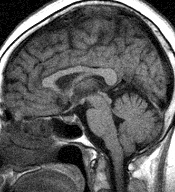

「血管の方の写真も撮っておきました。静脈瘤も動脈瘤もありません。」

こちらも正常。

「では、蜘蛛膜下出血の心配はありませんね。」

と聞くと、

「絶対と言う事は言えませんが、可能性は少ないですね。」

とのこと。

右の写真は、これも借り物で私の写真では有りませんが、頭の中の血管ってすごいですね。私の写真は、この写真よりもう少し血管が太く、梅の古木の盆栽のようなイメージを感じましたが、写真の撮り方によるのかも知れません。